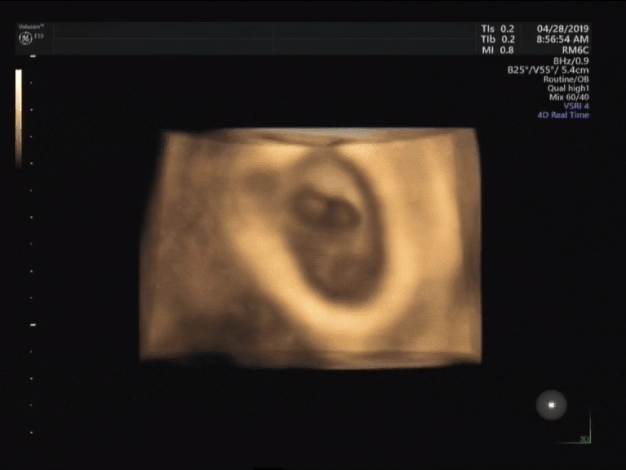

4月28日,天气晴朗,如同黄明兰(化名)夫妇一扫阴霾的心情。黄明兰一次又一次看着刚出的B超检查结果,仍不敢相信自己真的怀上了期盼已久的宝宝!

4月28日,黄明兰的B超结果出来了——宫内早孕,可见胎心搏动。这是市工人医院生殖医学中心通过“试管婴儿”技术试运行评审后第一对成功通过“试管婴儿”技术受孕的夫妇,也是第一对在梧州地区通过“试管婴儿”技术助孕成功的夫妇。黄明兰成功受孕,代表着梧州地区辅助生殖技术再次上升一个台阶,给不孕不育患者带来福音。(林芝 陈思晴)